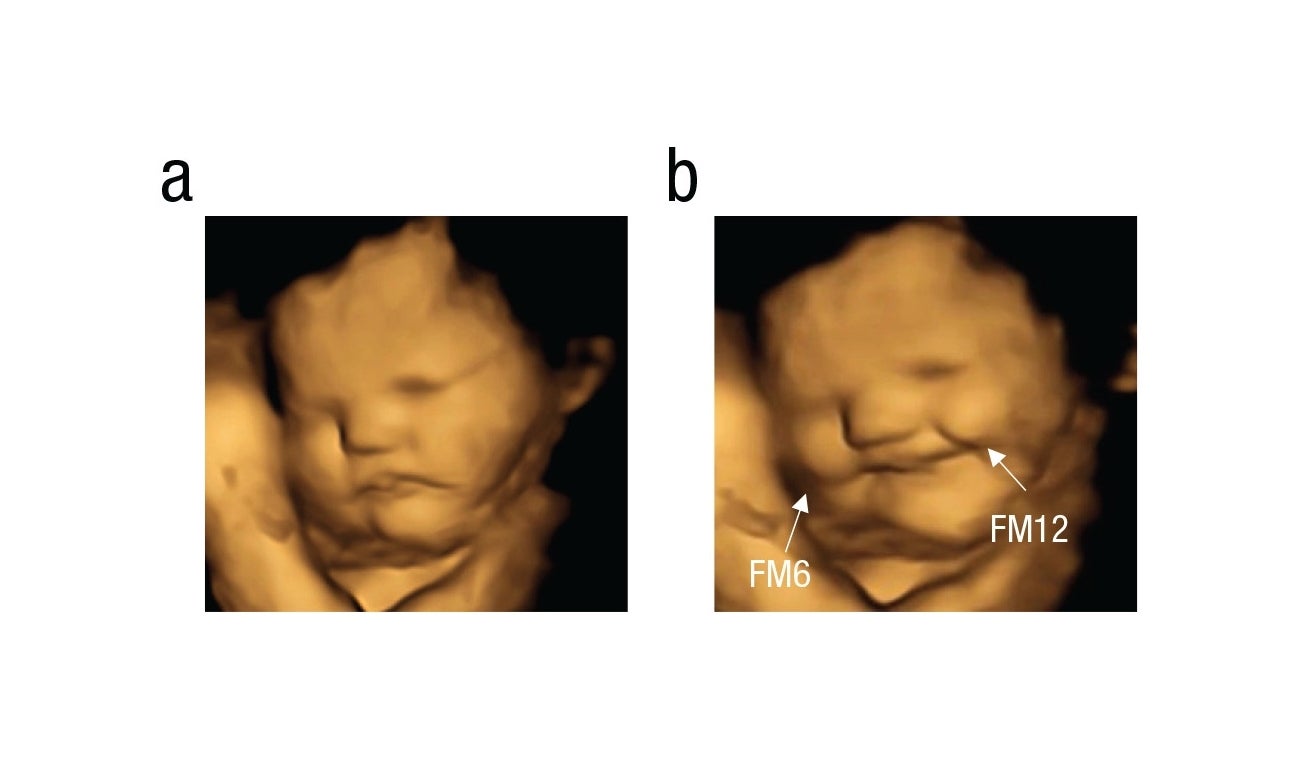

Aquellos que quedaron expuestos a la zanahoria hacían tirones de la comisura de los labios, lo que daba la impresión de que estuvieran sonriendo. Mientras que los expuestos a la col rizada hacían una mueca, como si estuvieran frunciendo el ceño.

Feto Col

Feto expuesto a la Col Rizada

Psychological Science

El experimento continúo cuando las madres llevaban entre 32 y 36 semanas de gestación al ver que las expresiones de los bebés que se expusieron a la col rizada se volvieron cada vez más complejas